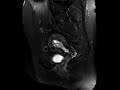

Tamoxifen associated endometrial hyperplasia

Patient with history of tamoxiofen use. MR images demonstrate expansion and thickening of the endometrium with multiple internal cysts, findings seen on both the T2 and T1 post-gadolinium images, and classic appearance for endometrial hyperplasia in the setting of tamoxifen use.